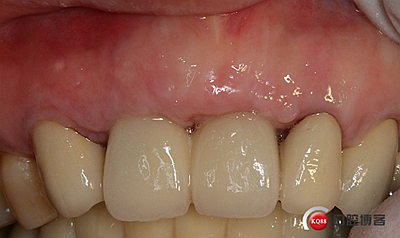

全瓷冠制作完成,齦乳頭預(yù)留空間不足,修整三角間隙。

戴牙。

戴牙后半年復(fù)查。